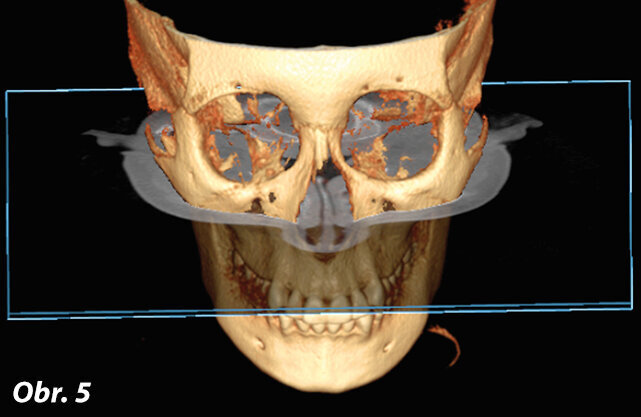

Transverzální rovina (obr. 5, 6)

Transverzální rovina je rovnoběžná s podlahou a okluzní rovinou. Rozděluje lebku na dvě stejné části: superiorní a inferiorní. Umožňuje prohlížet struktury směrem dolů a nahoru.